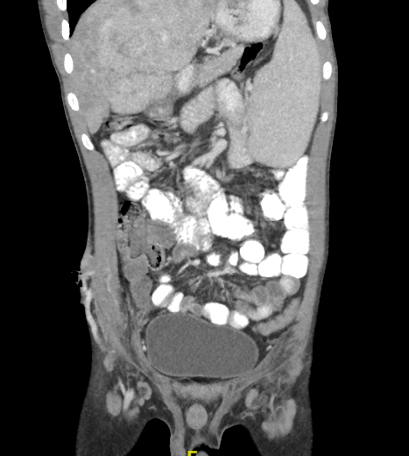

A 21-year-old man who was diagnosed with Budd-Chiari Syndrome 4 years earlier now presented with discharging sinus in the right iliac fossa for the past 2 years. There was a history of appendicitis and abscess formation 2 years ago for which he underwent percutaneous catheter drainage elsewhere. However, the catheter insertion site over the abdominal wall never healed and had persistent serosanguinous discharge for the past 2 years. On examination, the patient's vitals were unremarkable with no abdominal distension. Discharging sinus was seen over the right iliac fossa, which was oozing serosanguinous fluid (Figure 1). He was evaluated with ultrasonography of the abdomen and contrast-enhanced computed tomography (CECT) of the abdomen, which showed a dilated venous channel in continuity with the superior mesenteric vein, in the retroperitoneum anterior to the inferior aspect of the psoas, which are seen communicating with abnormally dilated venous channels over the discharging sinus in the right iliac fossa (Figure 2). The liver showed occluded native hepatic veins with collaterals draining into the inferior vena cava. No ascites was seen. The portal vein was prominent and splenomegaly was seen (Figure 3).